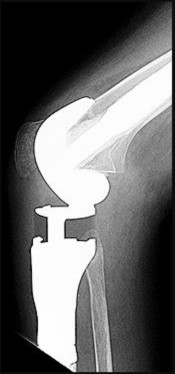

Question 14:

During a posterior-stabilized total knee arthroplasty, the surgeon assesses the flexion and extension gaps. The extension gap is symmetric and perfectly balanced, but the flexion gap is excessively tight. Which of the following is the most appropriate surgical adjustment?

Options:

- Resect more proximal tibia

- Downsize the femoral component to decrease the anteroposterior dimension

- Release the posterior cruciate ligament (PCL)

- Release the posterior capsule

- Increase the distal femoral resection

Correct Answer: Downsize the femoral component to decrease the anteroposterior dimension

Explanation:

When the extension gap is balanced but the flexion gap is tight, the goal is to increase the flexion gap without altering the extension gap. This can be achieved by decreasing the anteroposterior (AP) size of the femoral component, translating the femoral component anteriorly, or recessing the PCL (if retaining it, though this is a PS knee so PCL is already gone). Resecting more proximal tibia affects both gaps. Downsizing the AP femur size uniquely increases the flexion gap.